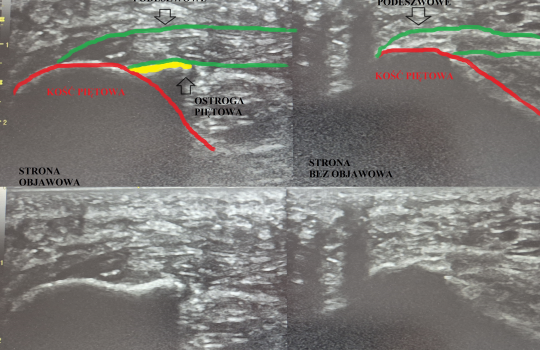

Ból pięty, który nie mija? Zobacz różnicę w USG i dowiedz się, jak skutecznie leczyć ostrogę piętową

Diagnostyka USG